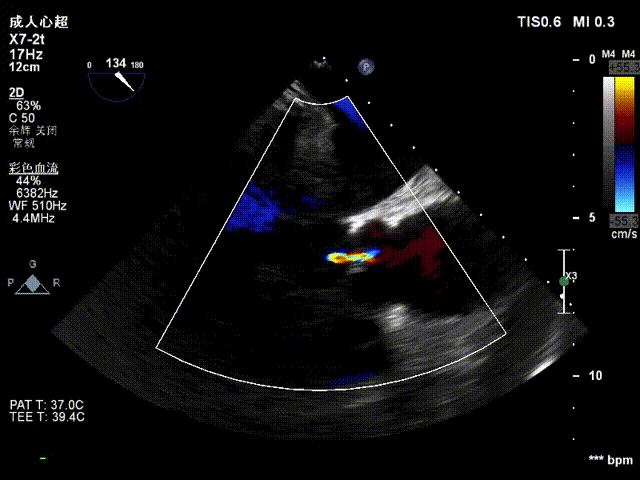

患者女性,62岁,以“间断胸闷、气短11年,加重8天”为主诉入院。经心脏超声检查,测辦口面积1.26cm²,主动脉辦上流速Vmax3.22m/s,平均跨瓣压差PG42mmHg。

超声提示:

主动脉瓣狭窄(中度)伴关闭不全(中度);

超声评估:

术后超声提示:主动脉瓣无瓣周漏